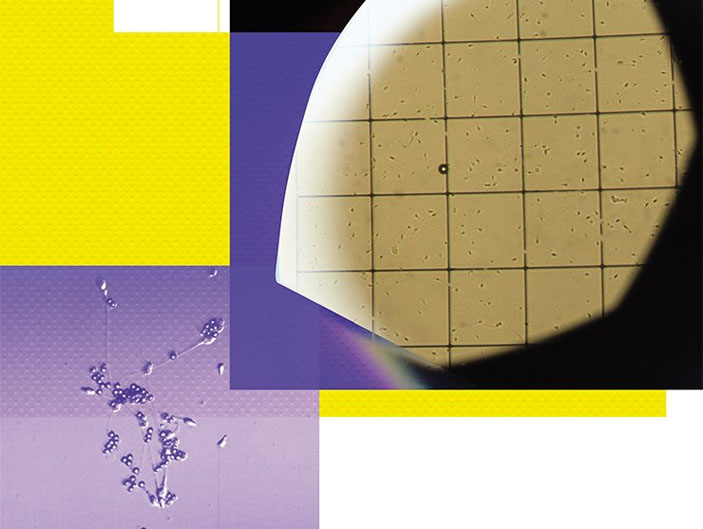

Интенсивность выработки антител к собственным сперматозоидам пациента определяют с помощью MAR-теста. Для этого к сперме добавляют латексные шарики, которые «прилипают» к сперматозоидам, покрытым антителами, что хорошо заметно под микроскопом (слева). Для спермограммы в первую очередь проводят микроскопический анализ эякулята, который позволяет определить концентрацию сперматозоидов и их подвижность, а также показатели других клеточных компонентов спермы (справа). Фото Е. Кирс (Новосибирский центр репродуктивной медицины)

На основе исследования около 3 тыс. супружеских пар было показано, что высокий уровень фрагментации ДНК сперматозоидов значительно увеличивает вероятность выкидыша (Robinson et al., 2012). На фото — анализ эякулята пациента с бесплодием. Фото Е. Кирс (Новосибирск)